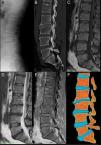

The patient was a 39-year-old farmer who had nothing remarkable in his clinical history. He presented with self-limiting, chronic, mechanical low back pain, without radiation, fever or systemic symptoms. Physical examination revealed only pain on palpation of the lumbar spinous processes and limited anterior dorsiflexion. Laboratory values, including serological findings and protein profile, were normal. A radiograph of the lumbar spine (Fig. 1A) showed an irregular sclerotic lesion in the epiphysis of lumbar 3 (L3). Lumbar computed tomography (Fig. 1B) showed irregularity, crush fracture and fragmentation preceding L3. Magnetic resonance imaging of the lumbar spine (Fig. 1C–E) revealed a limbus vertebra (LV) at L3, degenerative disc disease at L2–L4 and L5–sacral 1 (S1) and disc herniation at L3–L4 and L5–S1.

Limbus vertebra: (A) lateral radiograph of lumbar spine. The image shows the irregularity of the superior and anterior corners of the vertebral body at lumbar 3 (L3). The L2–L3 intervertebral space is narrowed. There are small anterior osteophytic formations at L2 and L4. The density of the vertebral bodies is conserved; (B) computed tomography with sagittal multiplanar reconstruction, in which the irregularity of the anterosuperior margin of L3 vertebral body can be seen in greater detail. Sclerosis can be observed both in the recessed vertebral endplates and around the osseous fragments separated from the rest of the bone. Listhesis can also be detected at L3–sacral 1 (S1) and Schmorl's node in the superior endplate at L1; (C) magnetic resonance imaging (MRI) of sagittal spin-echo T1-weighted (SET1) sequences. The intensity of the vertebral bodies is conserved and the osseous fragment separated from the L3 body has the same signal intensity has the rest of the bone; (D) MRI of sagittal spin-echo T2-weighted sequences. The findings complement what can be observed in the SET1 sequence. There is a decrease in height and signal of intervertebral discs at L2–L3, L3–L4 and L5–S1 in relation to dehydration in the setting of a degenerative disc disease. There is also a posterior central disc herniation at L5–S1, that migrated cranially, accompanied by listhesis; (E) MRI sagittal SET1 sequences in-phase and out-of-phase. In these sequences, the signal of the disc cartilage is high and bright. It can be seen how it is introduced between the osseous fragment and the foremost region of the superior L3 endplate; (F) drawing representing the changes observed in the images to the left. It can be seen that the L2–L3 intervertebral disc is introduced through the anterior surface of the L3 vertebral body. A Schmorl node can also be seen in the superior endplate of L1 and a protrusion of the L5–S1 disc, with a posterior central disc herniation, accompanied by listhesis at L5–S1.

Limbus vertebra is a radiological finding. Its prevalence is unknown and its significance is uncertain. It is a bone defect that affects the vertebral body margin, which is the origin of this a triangular fragment with sclerotic borders (Fig. 1F). It is produced in the form of an intraosseous herniation of the nucleus pulposus through the vertebral ring apophysis, prior to the complete fusion of the vertebral body. Its pathogenesis is related to that of Schmorl's nodes and Scheuermann disease. The most common localization is the lumbar spine and it involves the anterosuperior corner, followed by the anteroinferior region. Posterior LV is less frequent, but has a more marked clinical and functional impact because the osseous fragments can move, thus narrowing the spinal canal.1,2